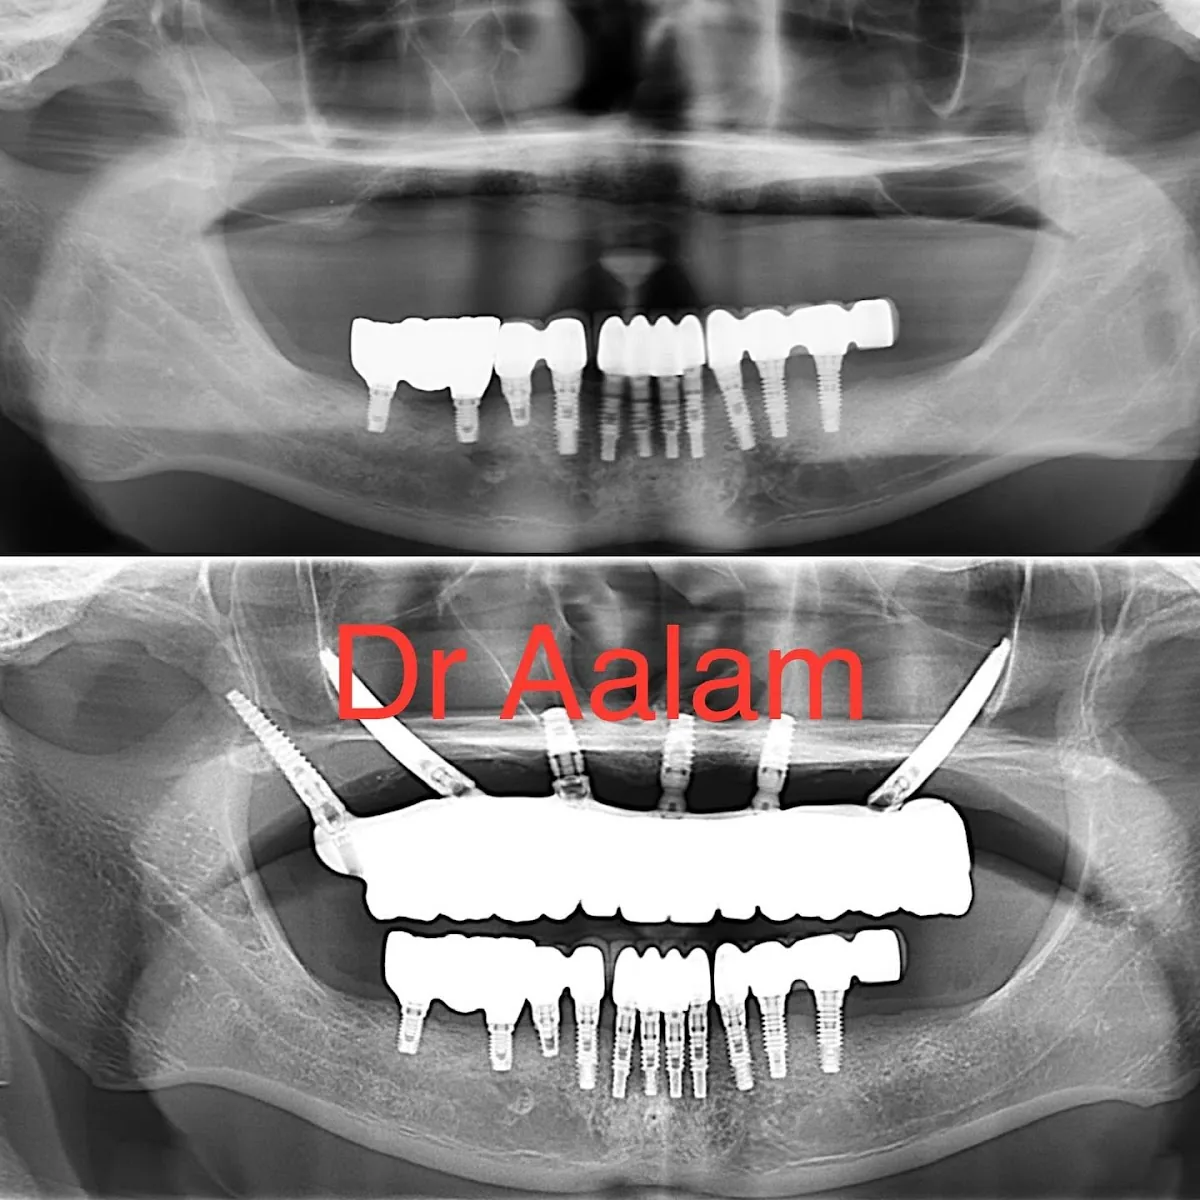

Dental Implants, Periodontics, Bone Grafting, APRF Therapy

Complex implant cases, Full-arch reconstruction, Bone grafting, Gum disease treatment

Patients needing complex implant surgery, Full-mouth reconstruction candidates, Cases requiring bone grafting